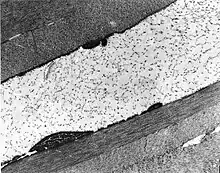

| The cornea is particularly opaque in the anterior stroma by slit-lamp biomicroscopy. | |